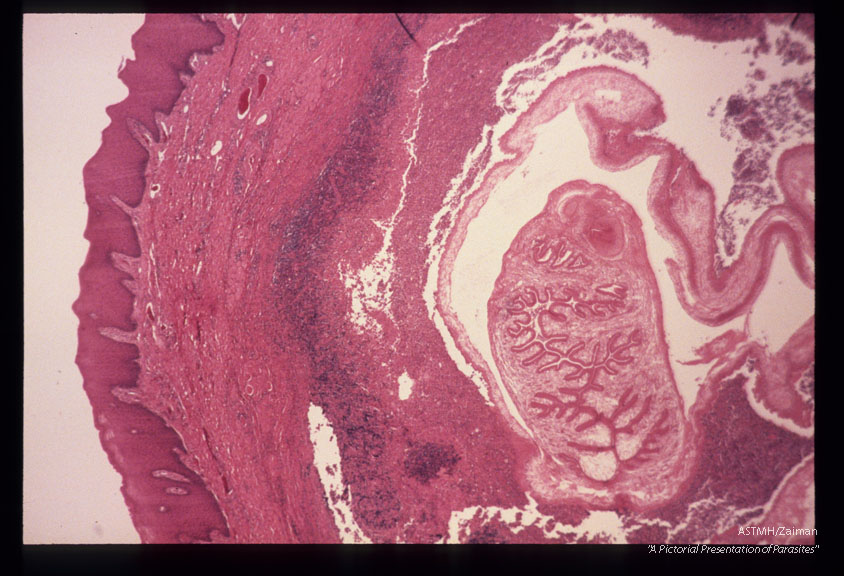

Low and high power views of cysticercus removed from buccal mucosa of patient.

Taenia solium

Description: Low and high power views of cysticercus removed from buccal mucosa of patient.